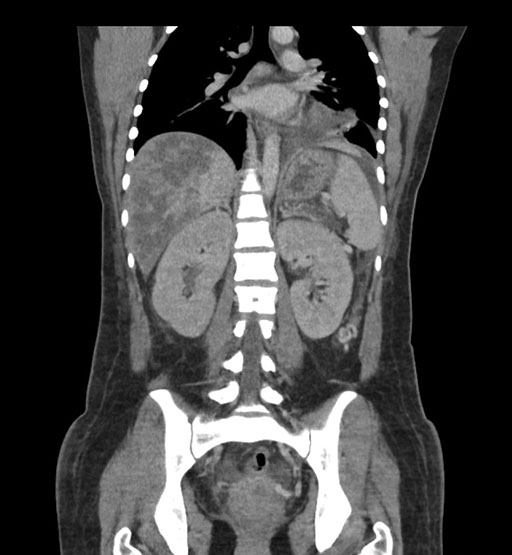

Imaging Analysis

Look through the patient's CT scan to identify any areas of concern for the necessary procedure.

Axial Venous